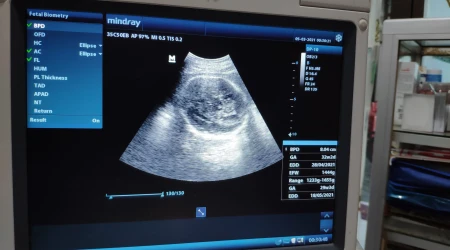

En términos prácticos, señala Polo, la nueva ley promueve políticas públicas que garantizan la cobertura sanitaria integral de la madre y el niño por nacer, incluyendo controles prenatales, nutrición materna, preparación para el parto, estimulación prenatal, atención del parto y postparto, descanso postnatal, estimulación temprana, prevención y diagnóstico precoz, atención temprana y rehabilitación, consejería y terapia familiar, así como educación para la salud y apoyo a la familia emprendedora.